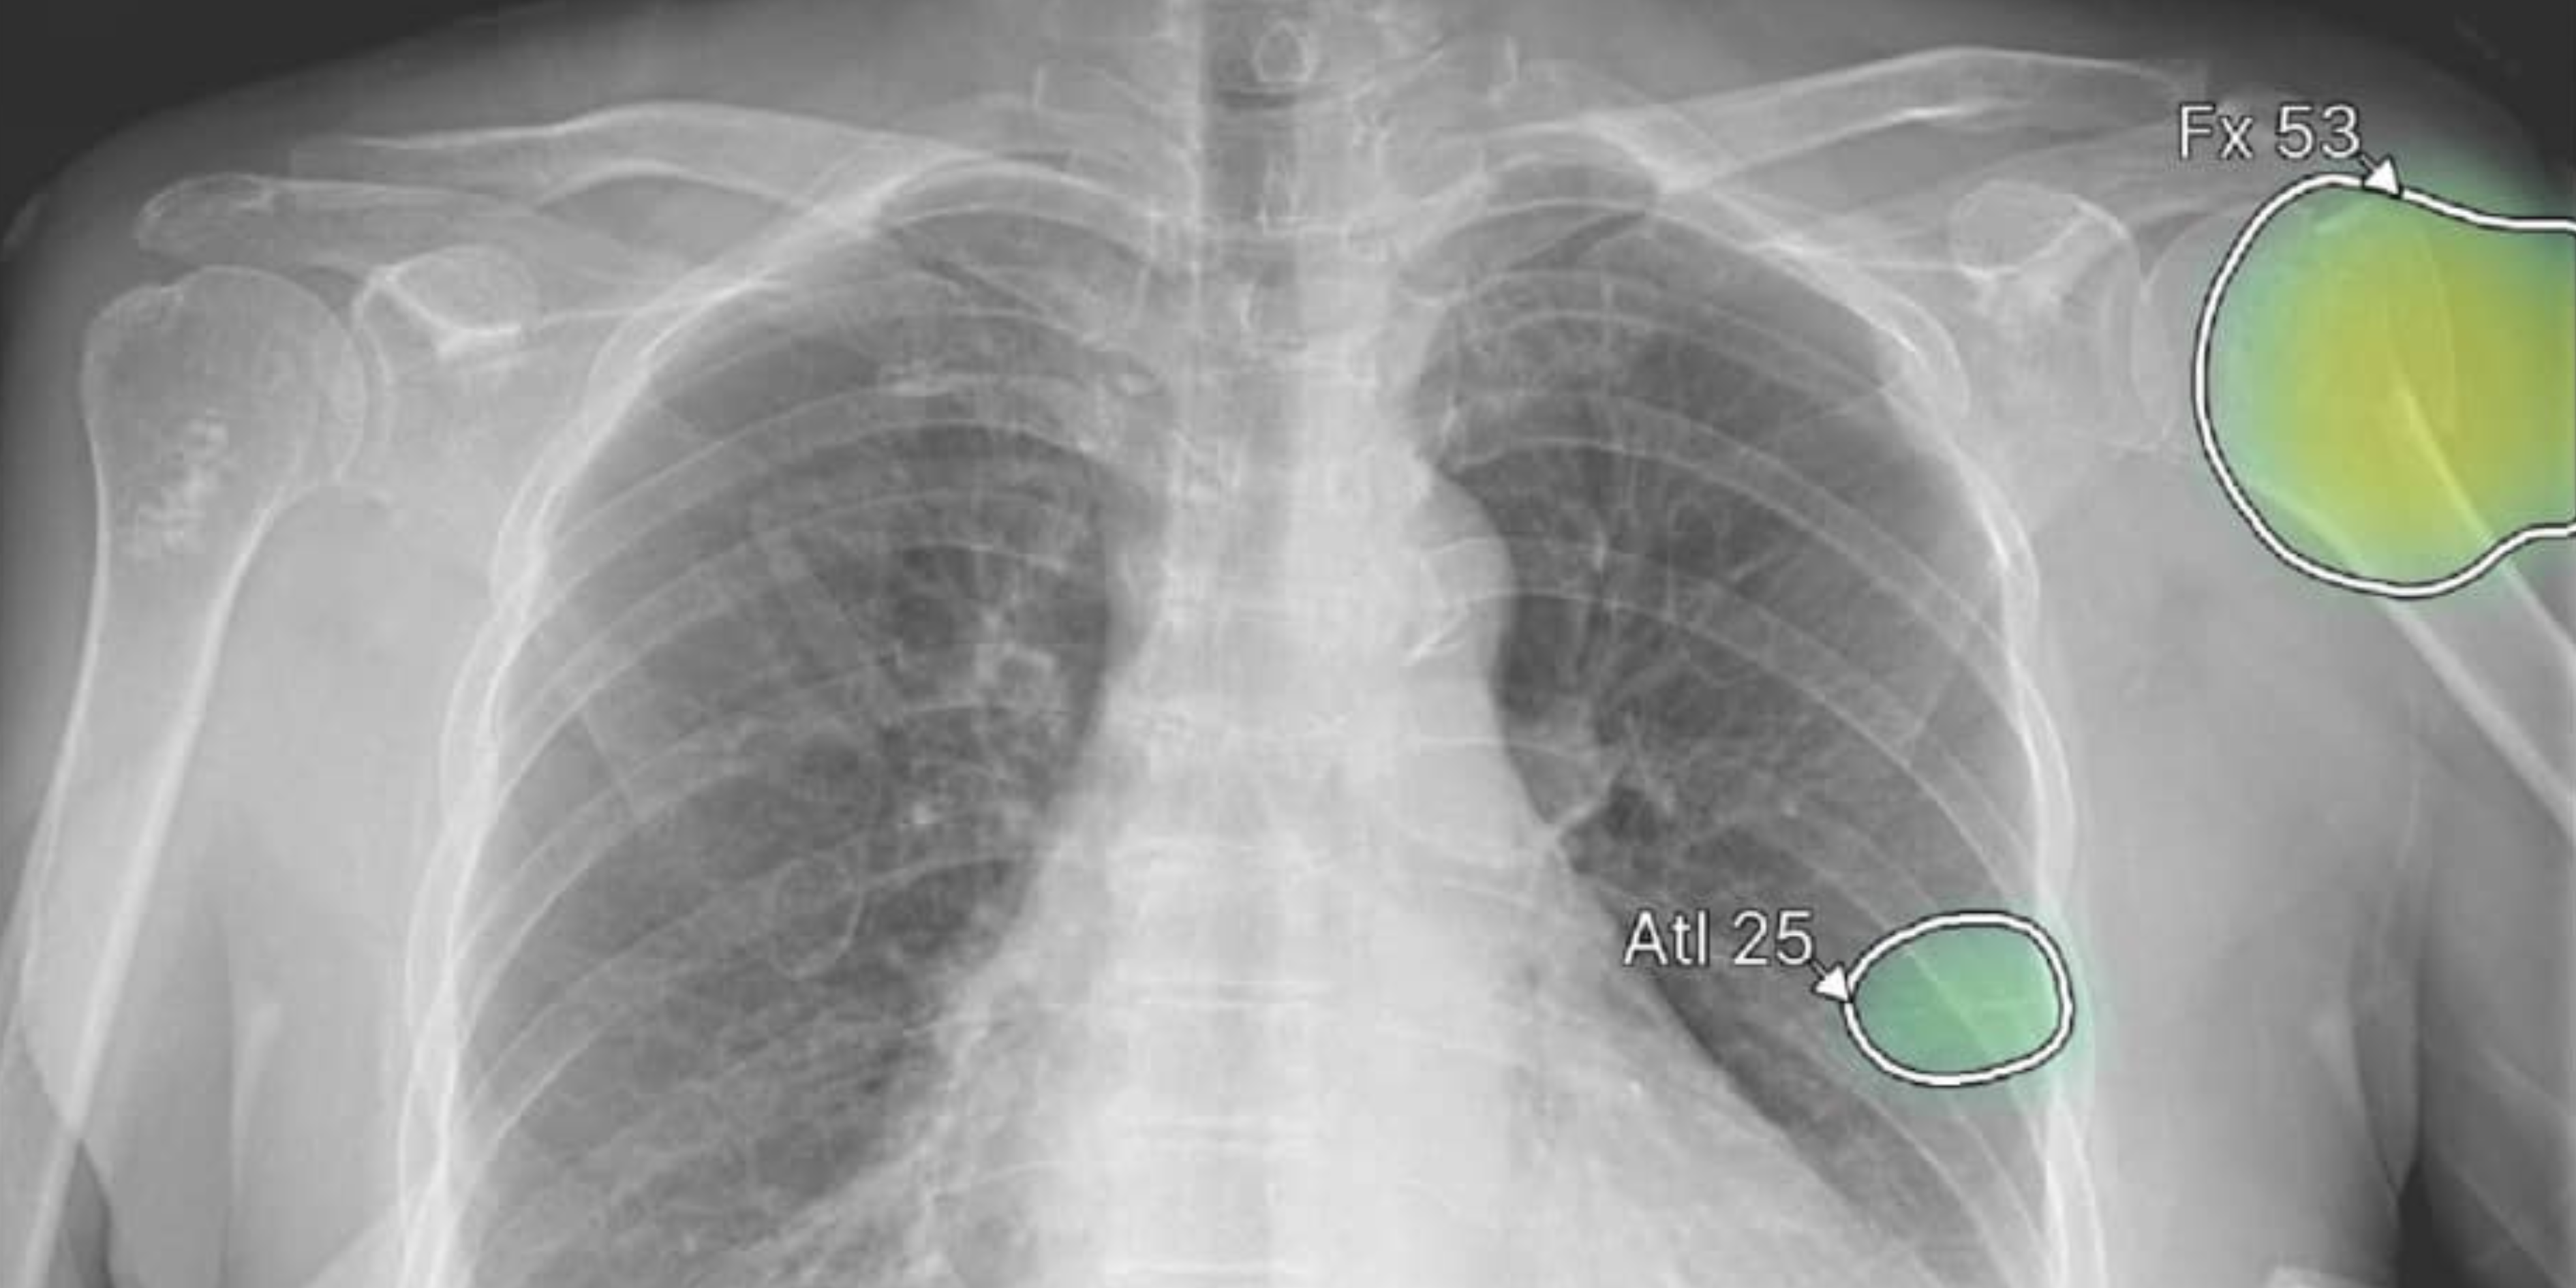

Los ciberataques en salud vienen creciendo a nivel global, con hospitales y sistemas completos afectados en distintos países, y el diagnóstico por imágenes es uno de los puntos más sensibles. Los sistemas almacenan millones de datos clínicos, funcionan muchas veces sobre infraestructura tecnológica envejecida y, en la mayoría de los casos, no cuentan con presupuesto suficiente para protegerse. Mientras otros sectores, como el financiero, invierten en seguridad desde hace décadas, muchos centros de salud avanzaron en digitalización sin la misma inversión en protección.